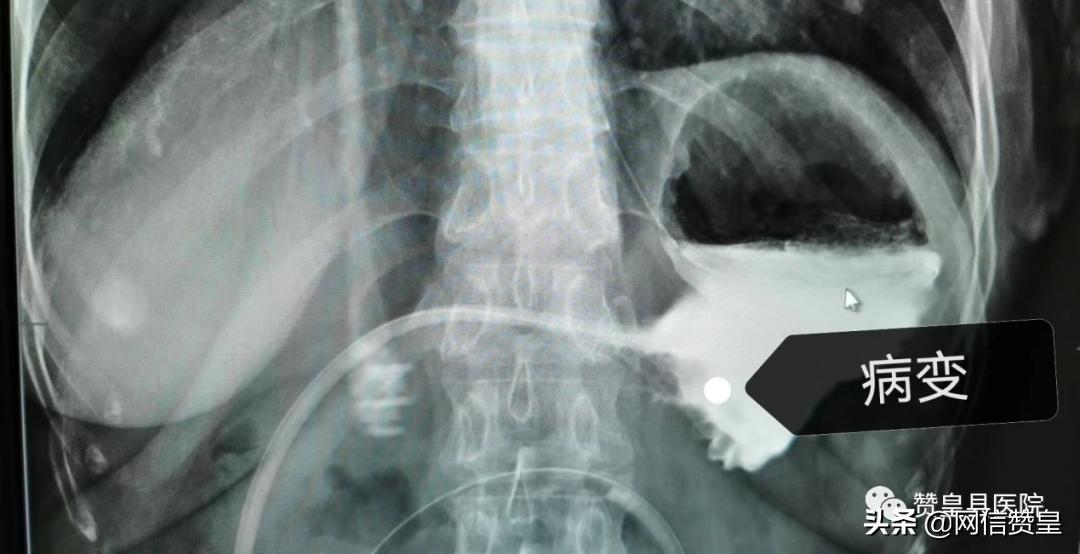

检查所见:病变已占据胃腔的一半,病人进食困难,全靠肠营养管维持。